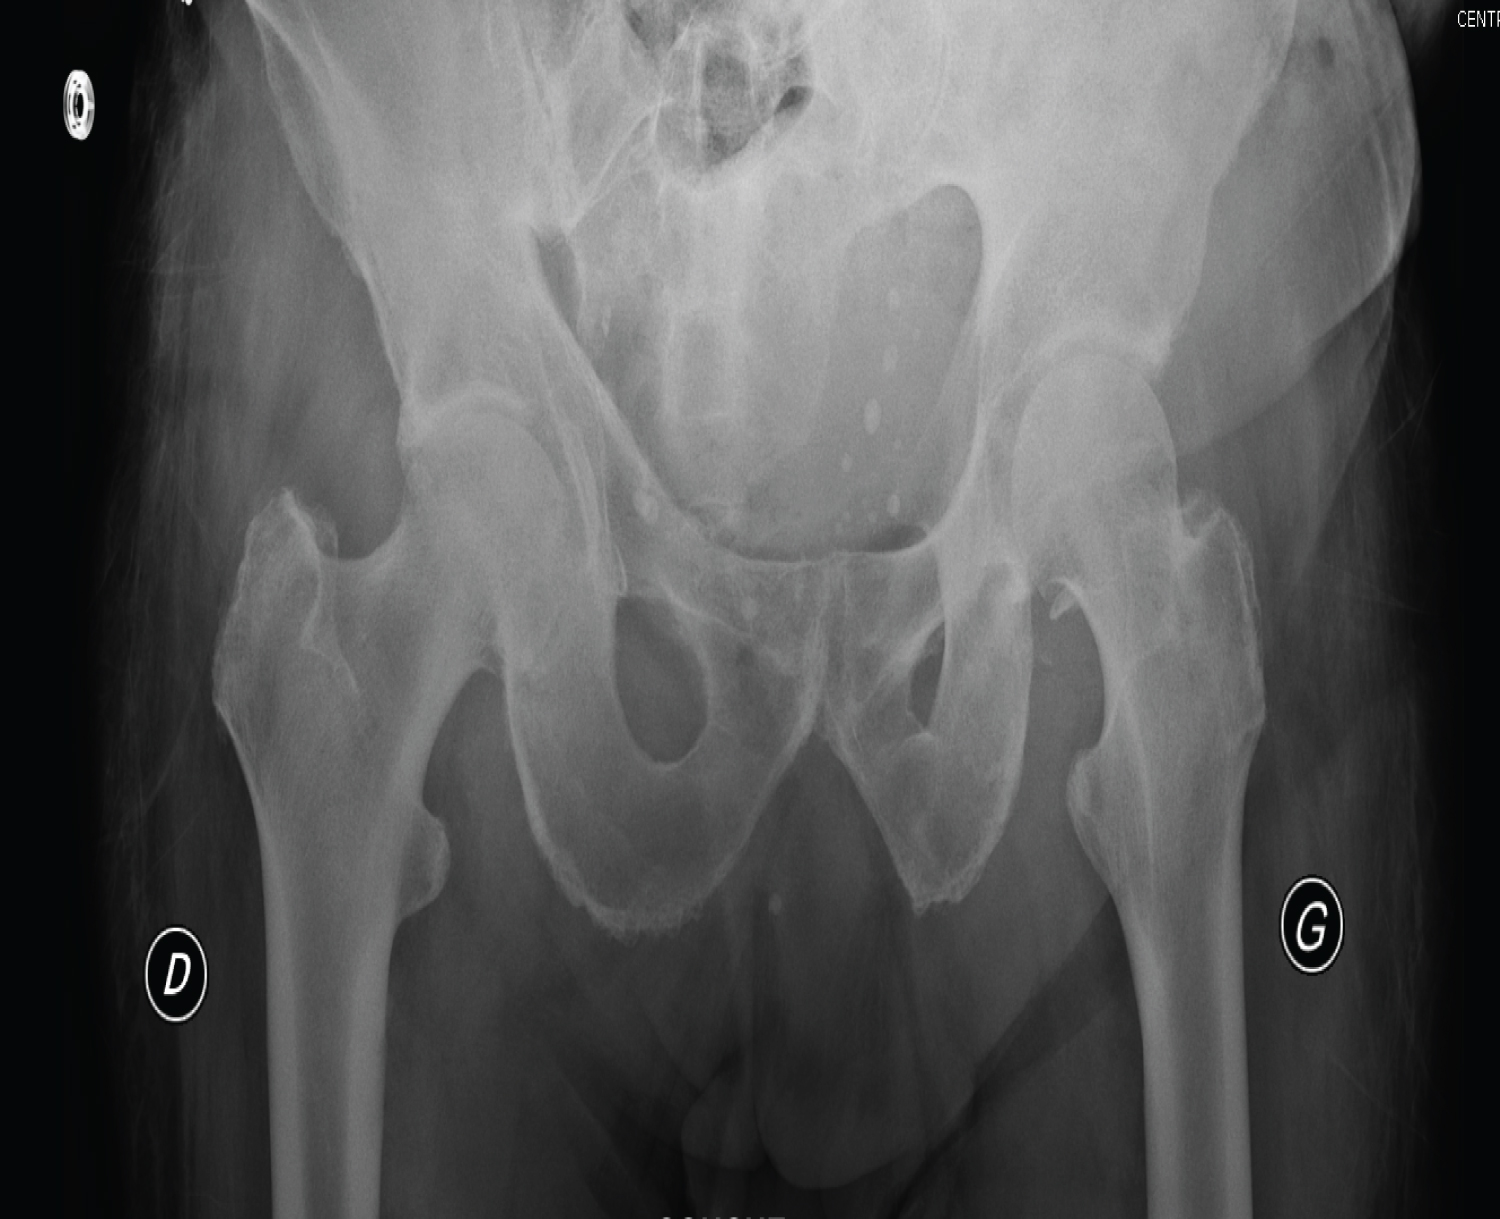

The radiographic assessment objectified a posterior dislocation of the left hip, and anterior on the right side, with no visible acetabular or femoral fracture (Figure 1). A CT scan of the pelvis was requested urgently which objectified a posterior dislocation of the left hip, and anterior on the right, without acetabular or femoral fracture, nor visible intra-articular foreign body (Figure 2), So it is a divergent bilateral dislocation of the two hips.

Figure 1: Radiological appearance of bilateral hip dislocation. View Figure 1